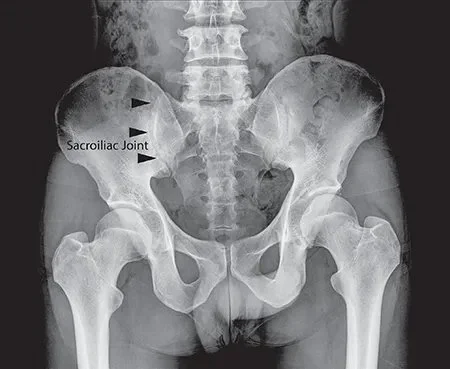

The sacroiliac joint is where the sacrum, the triangular bone at the base of the spine, connects to the ilium, or the “wings” of the pelvis. This joint is supported by strong ligaments, and its primary role is to provide stability and support for the upper body, particularly during activities like walking, lifting, and standing.

Here is an image of the SIJ using X-rays and demonstrates what it is we are looking at when assessing these joints through imaging: